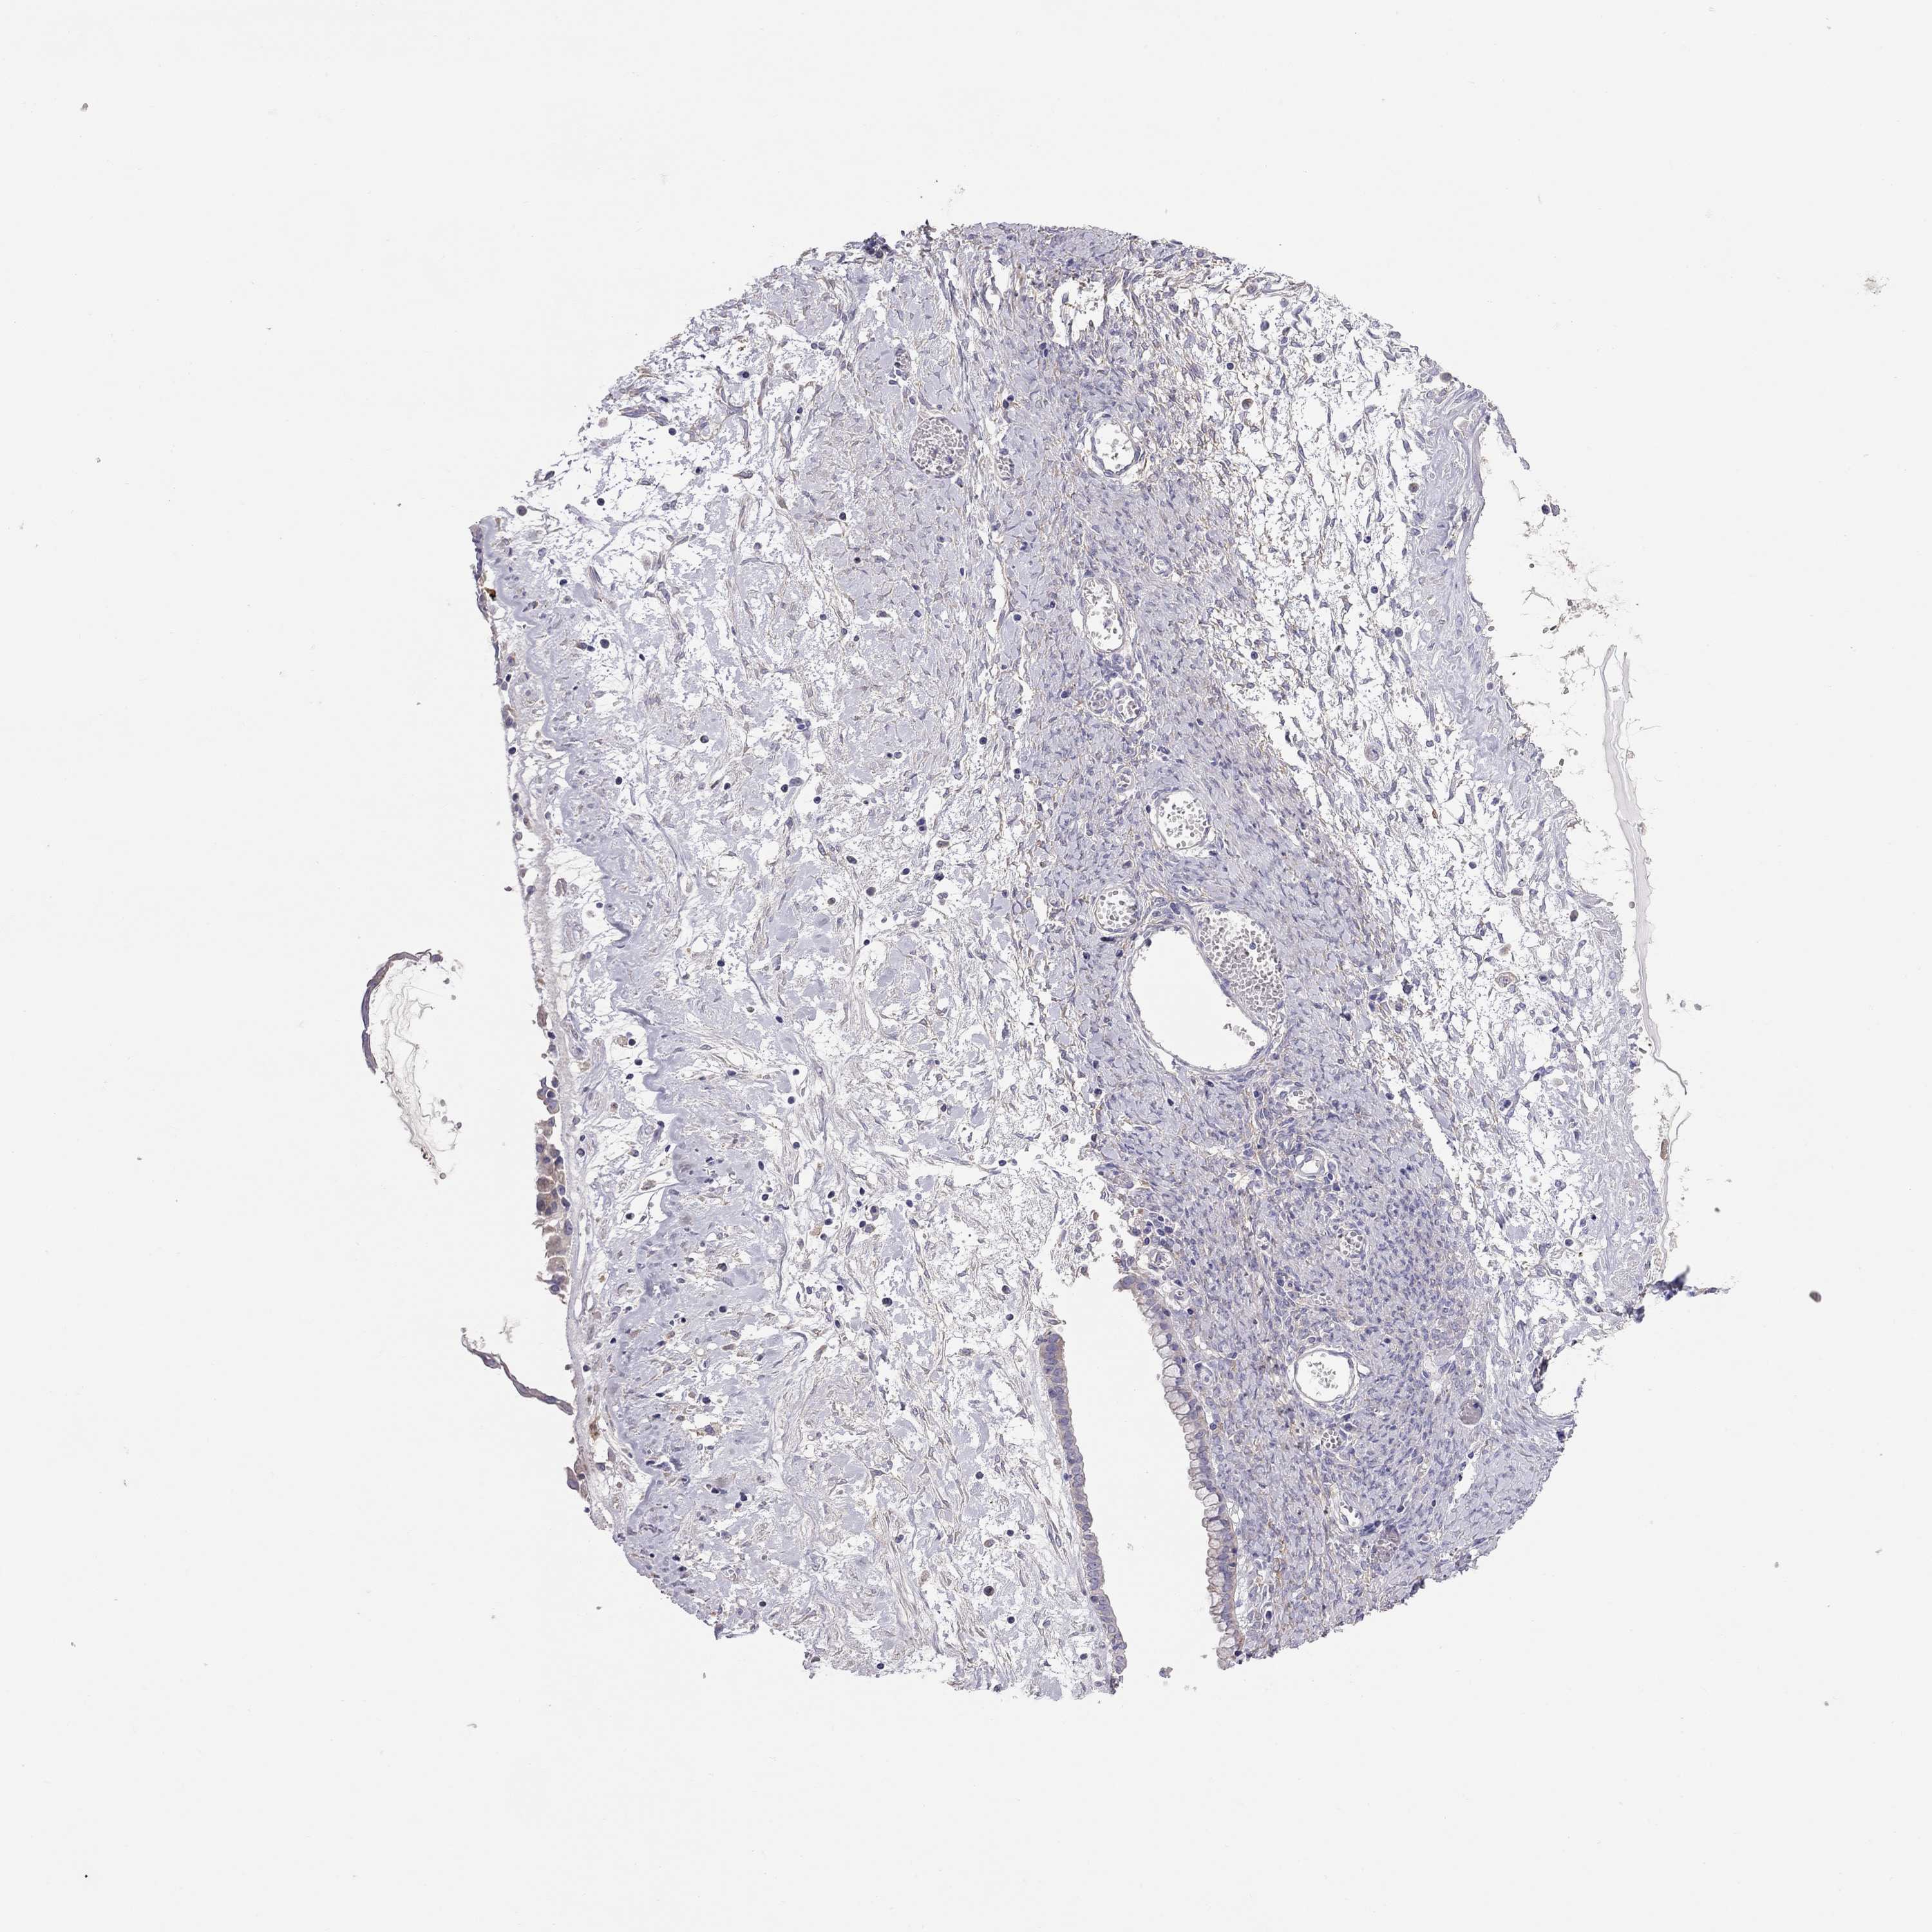

OVARIAN CANCER - Protein expressioni

A mouse-over function shows sample information and annotation data. Click on an image to view it in a full screen mode. Samples can be filtered based on level of antibody staining by selecting one or several of the following categories: high, medium, low and not detected. The assay and annotation is described here.

Note that samples used for immunohistochemistry by the Human Protein Atlas do not correspond to samples in the TCGA dataset.

Antibody stainingi

Antibody staining in the annotated cell types in the current human tissue is reported as not detected, low, medium, or high, based on conventional immunohistochemistry profiling in selected tissues. This score is based on the combination of the staining intensity and fraction of stained cells.

Each image is clickable and will lead to virtual microscopy that enables deeper exploration of all samples and also displays staining intensity scores, fraction scores and subcellular localization as well as patient and tissue information for each sample.

Antibody HPA010562

Cystadenocarcinoma, serous, NOS

Cystadenocarcinoma, mucinous, NOS

Carcinoma, endometroid